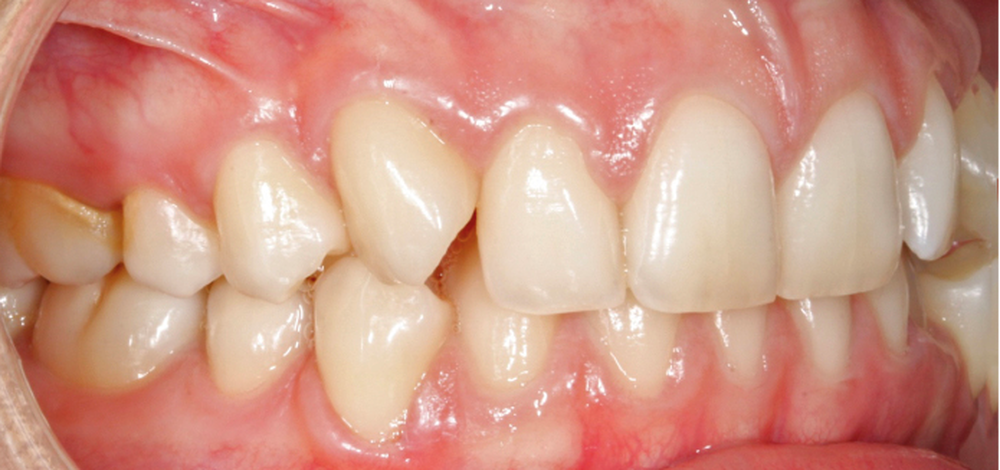

L’examen intra-arcade met en évidence une hygiène bucco-dentaire irréprochable, favorable à un traitement en technique linguale. Le phénotype parodontal est fin dans la région incisivo-canine mandibulaire. L’encombrement est estimé à 8 mm à la mandibule et à 4 mm au maxillaire (fig. 1). Les arcades ont des formes similaires, en U. Les rapports inter-arcades mettent en évidence une classe 1 d’Angle molaire, une classe 2 d’Angle canine et une supraclusion antérieure (recouvrement : 5 mm ; surplomb diminué). Les milieux inter-incisifs sont déviés entre eux avec une origine mixte (= 1,5 mm) (fig. 2).